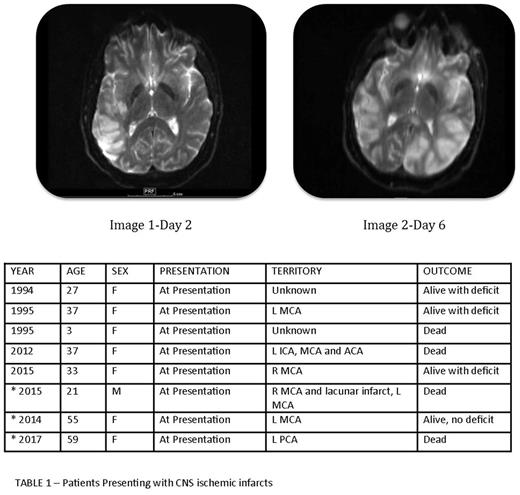

On review of the literature, five cases were described where patients with newly diagnosed APL presented with CNS arterial thrombosis; 3 patients are alive with neurologic deficit and 2 are dead. (Table 1).

We have experience with three patients diagnosed with APL who presented with cerebrovascular infarct. We report our experience to heighten awareness of this unusual presentation of this rare type of leukemia.